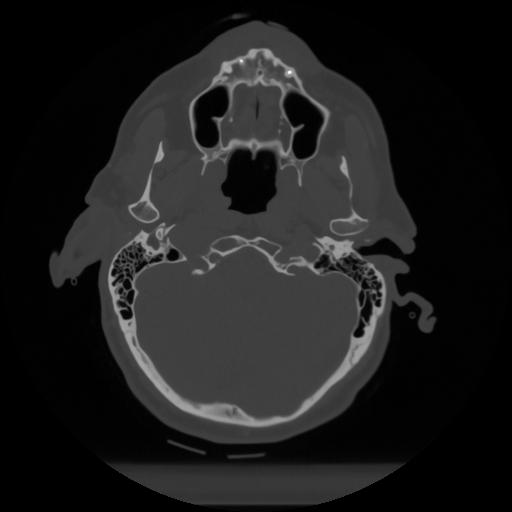

12 P.BLANDAS,,Vol,0.5,P.BLANDAS,,